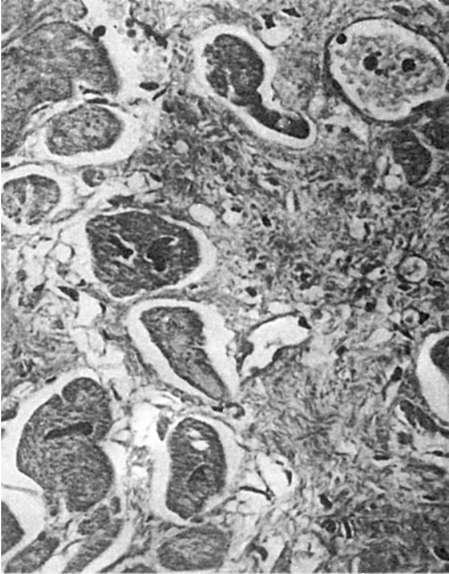

Восстановление исходной массы органа и его функции за счет преимущественно гиперплазии клетокпроисходит при регенерационной гипертрофии печени, почек, поджелудочной железы, надпочечников, легких, селезенки и др. Регенерационная гипертрофия за счет гиперплазии клеточных ультраструктур характерна для миокарда, головного мозга, т.е. тех органов, где преобладает внутриклеточная форма регенерации. В миокарде, например, по периферии рубца, заместившего инфаркт, размеры мышечных волокон значительно увеличиваются, т.е. они гипертрофируются в связи с гиперплазией их субклеточных элементов (рис. 81). Оба пути регенерационной гипертрофии не исключают друг друга, а, наоборот, нередко сочетаются. Так, при регенерационной гипертрофии печени происходит не только

Рис.

81. Регенерационная гипертрофия миокарда. По периферии рубца расположены гипертрофированные мышечные волокна